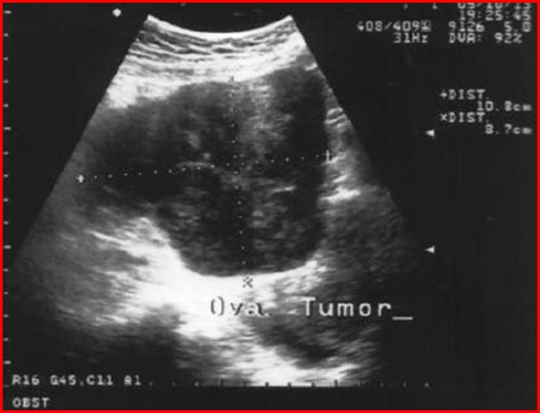

On the other hand, the literature reports cases of ovarian Burkitt lymphoma that were treated immediately by surgery, precisely because the diagnosis of lymphoma was not suspected. This is the case described in Szu-Ching Lu et al [10] who describe the appearance of ovarian Burkitt’s lymphoma in a 50-year-old woman. Unfortunately, the woman does not present with the common systemic symptoms of lymphoma such as fever, night sweats, nausea, vomiting or bladder symptoms. His Pap test was normal and on physical examination, as in the cases described previously, a pelvic mass of the size of approximately 20 weeks of gestation was revealed. The high resolution trans-vaginal ultrasound examination revealed a large and homogeneous abdominal mass measuring 10.8 x 8.7 cm extending from the uterus to the left ovary and the presence of a minimal content of free liquid (Figure17-18 ). Power-Doppler ultrasound showed no vascularity in the mass. All blood tests, including tumor markers, were normal before surgery.

Figure 17: Trans-abdominal ultrasound showing a large irregularly shaped echogenic pelvic mass. The mass measures 10.8 x 8.7 cm.

Figure 18: Trans vaginal ultrasound showing a large pelvic mass, extending from the right anterior wall of the uterus, with homogeneous echogenicity and some small anechoic areas within the mass.